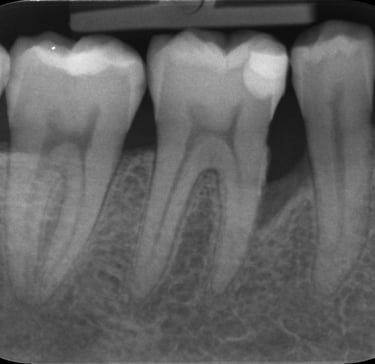

Parodontologie pour l'omnipraticien

Diagnostic et traitement